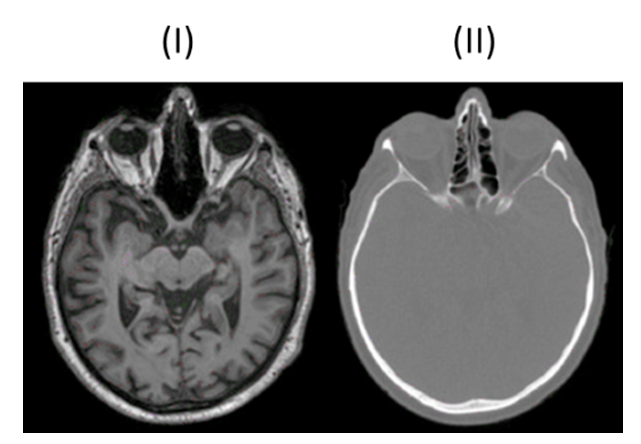

MRT (Bild I)

Strahlenfrei

hohe Bildqualität

Weichteildarstellung

Flexibilität bei Schnittführung

MRT (Bild I) typische Merkmale

Erzeugung Graustufenbildern basierend auf Anregung der Wasserstoffprotonen im Gewebe

T1-Wichtung: Hervorhebung fetthaltiger Strukturen → Knochen schwarz, Fettgewebe weiß

T2-Wichtung: Hervorhebung wasserhaltiger Strukturen → Liquor weiß, weiße Substanz dunkelgrau

CT (Bild II)

CT (Bild II) typische Merkmale

Weniger Kontrast bei Weichgewebe

Weiße Knochen